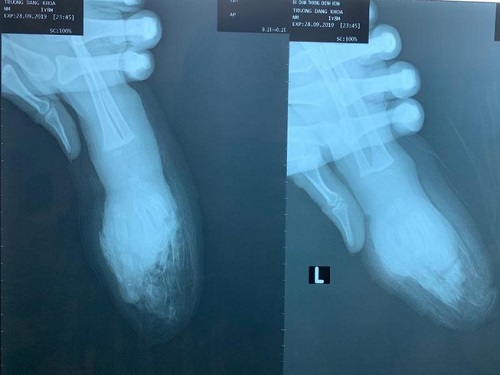

Giữa bàn tay trái cùng bốn ngón tay bé K. bị đứt lìa - Ảnh: Pháp luật TP. HCM |

Chiều 3/10, BS Võ Hòa Khánh, Trưởng phòng Quản lý chất lượng BV Chấn thương chỉnh hình TP.HCM, cho biết nơi đây vừa cứu bàn tay trái cùng bốn ngón tay đứt lìa cho bé trai TĐK (một tuổi, ngụ Đồng Tháp).

Trước đó, BV tiếp nhận bé K. trong tình trạng đứt lìa ngang giữa bàn tay trái. Các ngón 2, 3, 4 và 5 của bàn tay bị đứt lìa, vết thương bầm dập nhiều.

Mẹ bé K. cho biết gia đình mới mua xe máy nên cho chạy rô đa. Trong lúc mọi người không chú ý, bé K. bò tới đút tay trái vô dây sên nên bị cuốn và bị cắt đứt lìa ngang giữa bàn tay cùng bốn ngón. Gia đình đưa bé K. vào BV địa phương sơ cứu rồi đưa lên BV chuyên khoa nhi ở TP.HCM. Sau đó bé được chuyển đến BV Chấn thương chỉnh hình TP.HCM.

Các bác sĩ cắt rửa lọc vết thương và nối vi phẫu bốn ngón tay dưới kính hiển vi. Sau đó tiếp tục phẫu thuật nối phần ngang giữa bàn tay. Ca mổ thành công sau 8 tiếng.

Theo BS Khánh, hiện bàn tay trái cùng bốn ngón tay sống tốt. Tuy nhiên, bé K. vẫn tiếp tục được theo dõi nguy cơ nhiễm trùng, nguy cơ tắc mạch máu. “Đây là trường hợp bệnh nhi nhỏ tuổi nhất bị tai nạn thương tâm và nặng nề được ghi nhận tại BV Chấn thương chỉnh hình TP.HCM”, BS Khánh nói.